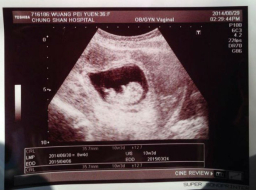

劉畊宏王婉霏懷第三胎 稱上帝所賜超乎所求